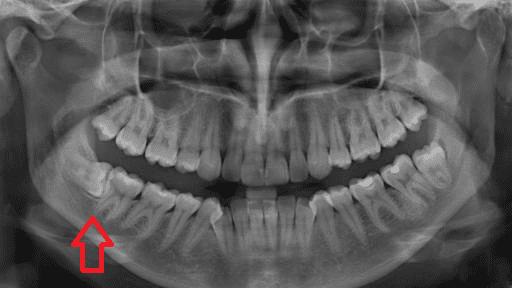

Дентальная галерея: ретинированный зуб клык и его лечение

Раздел: Компас решений